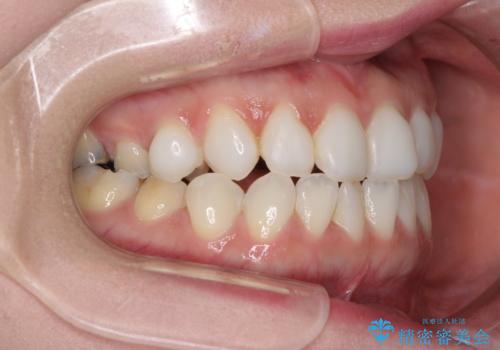

前歯のデコボコをすっきりと インビザライン矯正

- 前歯のデコボコを治したいとのことで来院された患者様です。

下顎が前方位にある方であったため、下顎の歯列全体の後方移動とIPR(歯と歯の間を削る)によってデコボコが解消するように設計し、インビザラインにより治療を行うこととしました。